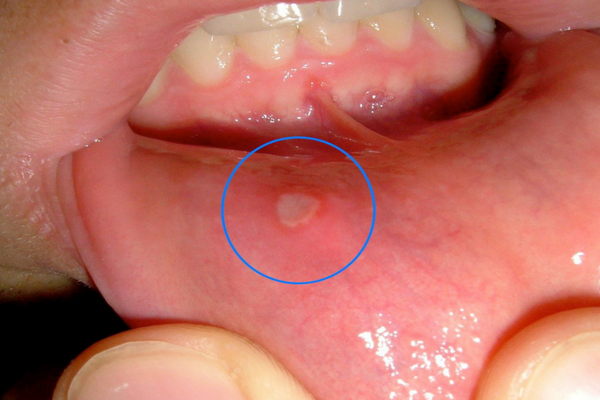

Stomatitis

fotovia wikipedia.org

Hal ini disebabkan oleh virus dan menyebabkan luka di mulut dan tenggorokan.

Sebenarnya penyakit ini bisa membaik dengan sendirinya, namun kondisinya membuat makan dan minum sangat tidak nyaman.

Ada obat yang bisa membantu melapisi luka dan membuat minum lebih mudah, untuk membantu mencegah dehidrasi.